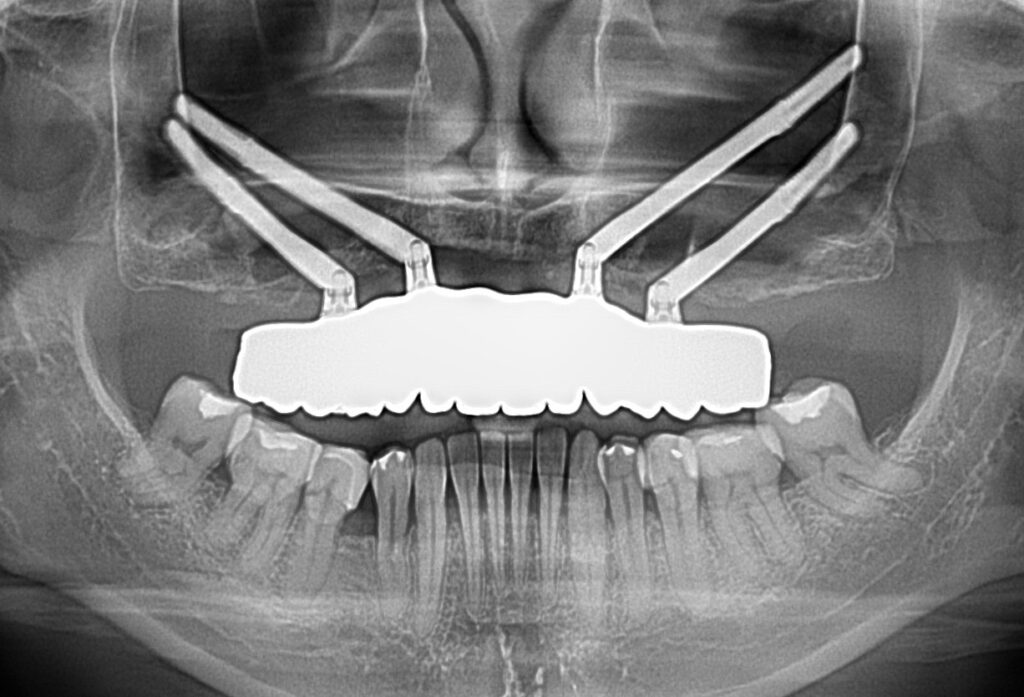

A selection of full arch fixed implant bridge patients after 5 years of wear

Oral Surgeons – Dr Han Choi, Dr Sam Goldsmith, Dr Rajiv Rajpal NSOMS

Prosthodontist – Dr Alan Payne NSOMS/Northland Prosthodontics

Dental technicians – Hosaka Takashi, DT Denture Design, Auckland, CJ Park, Project Dentistry, Auckland and Osteon Medical, Melbourne, Australia.